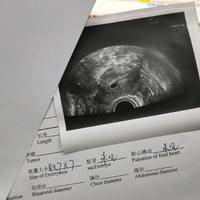

为什么试管移植后查出成功怀孕了要做3次B超?

问题描述:家里一直催生娃,我们已经结婚三年了,但都没有怀孕所以家里都催得比较急。然而我自己影响生育,但因为身体原因不能自然怀孕,后面和我老公商量去做试管了。幸运的是第一次移植后就查出来成功怀孕了,在这之后医生说还要做3次B超,这是为什么呢?最佳回答:试管怀孕后要做3次B超主要是因为胚胎在不同发育阶段都需要进行详细检测,以此来判断出胚胎发育是否存在异常。3次B超分别对应不同怀孕周期,而且每次检查重点...